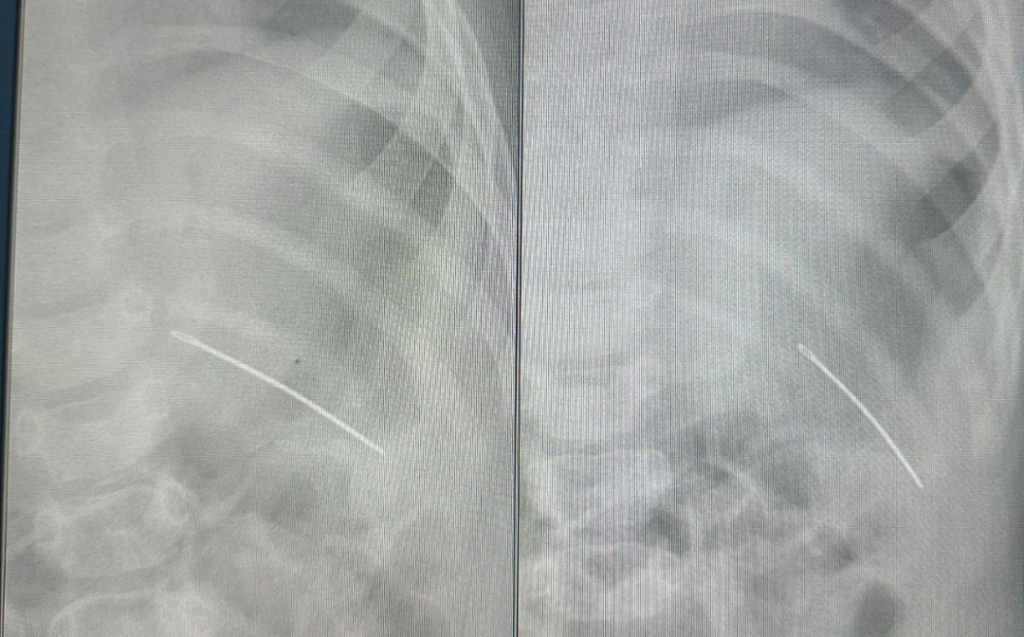

В Самаре хирурги успешно извлекли швейную иглу из грудной клетки восьмимесячного малыша. Об этом сообщили в региональном Минздраве.

Родители обратились к врачам из-за того, что их девочка сильно капризничала, поджимала ногу, а ее рука подвисала. В травмпункте специалисты провели диагностические исследования, по результатам которых в грудной клетке обнаружили иглу. Приняли решение о необходимости операции.

Хирурги благополучно удалили инородное тело, тем самым спасли жизнь ребенку.

Фото: Минздрав Самарской области